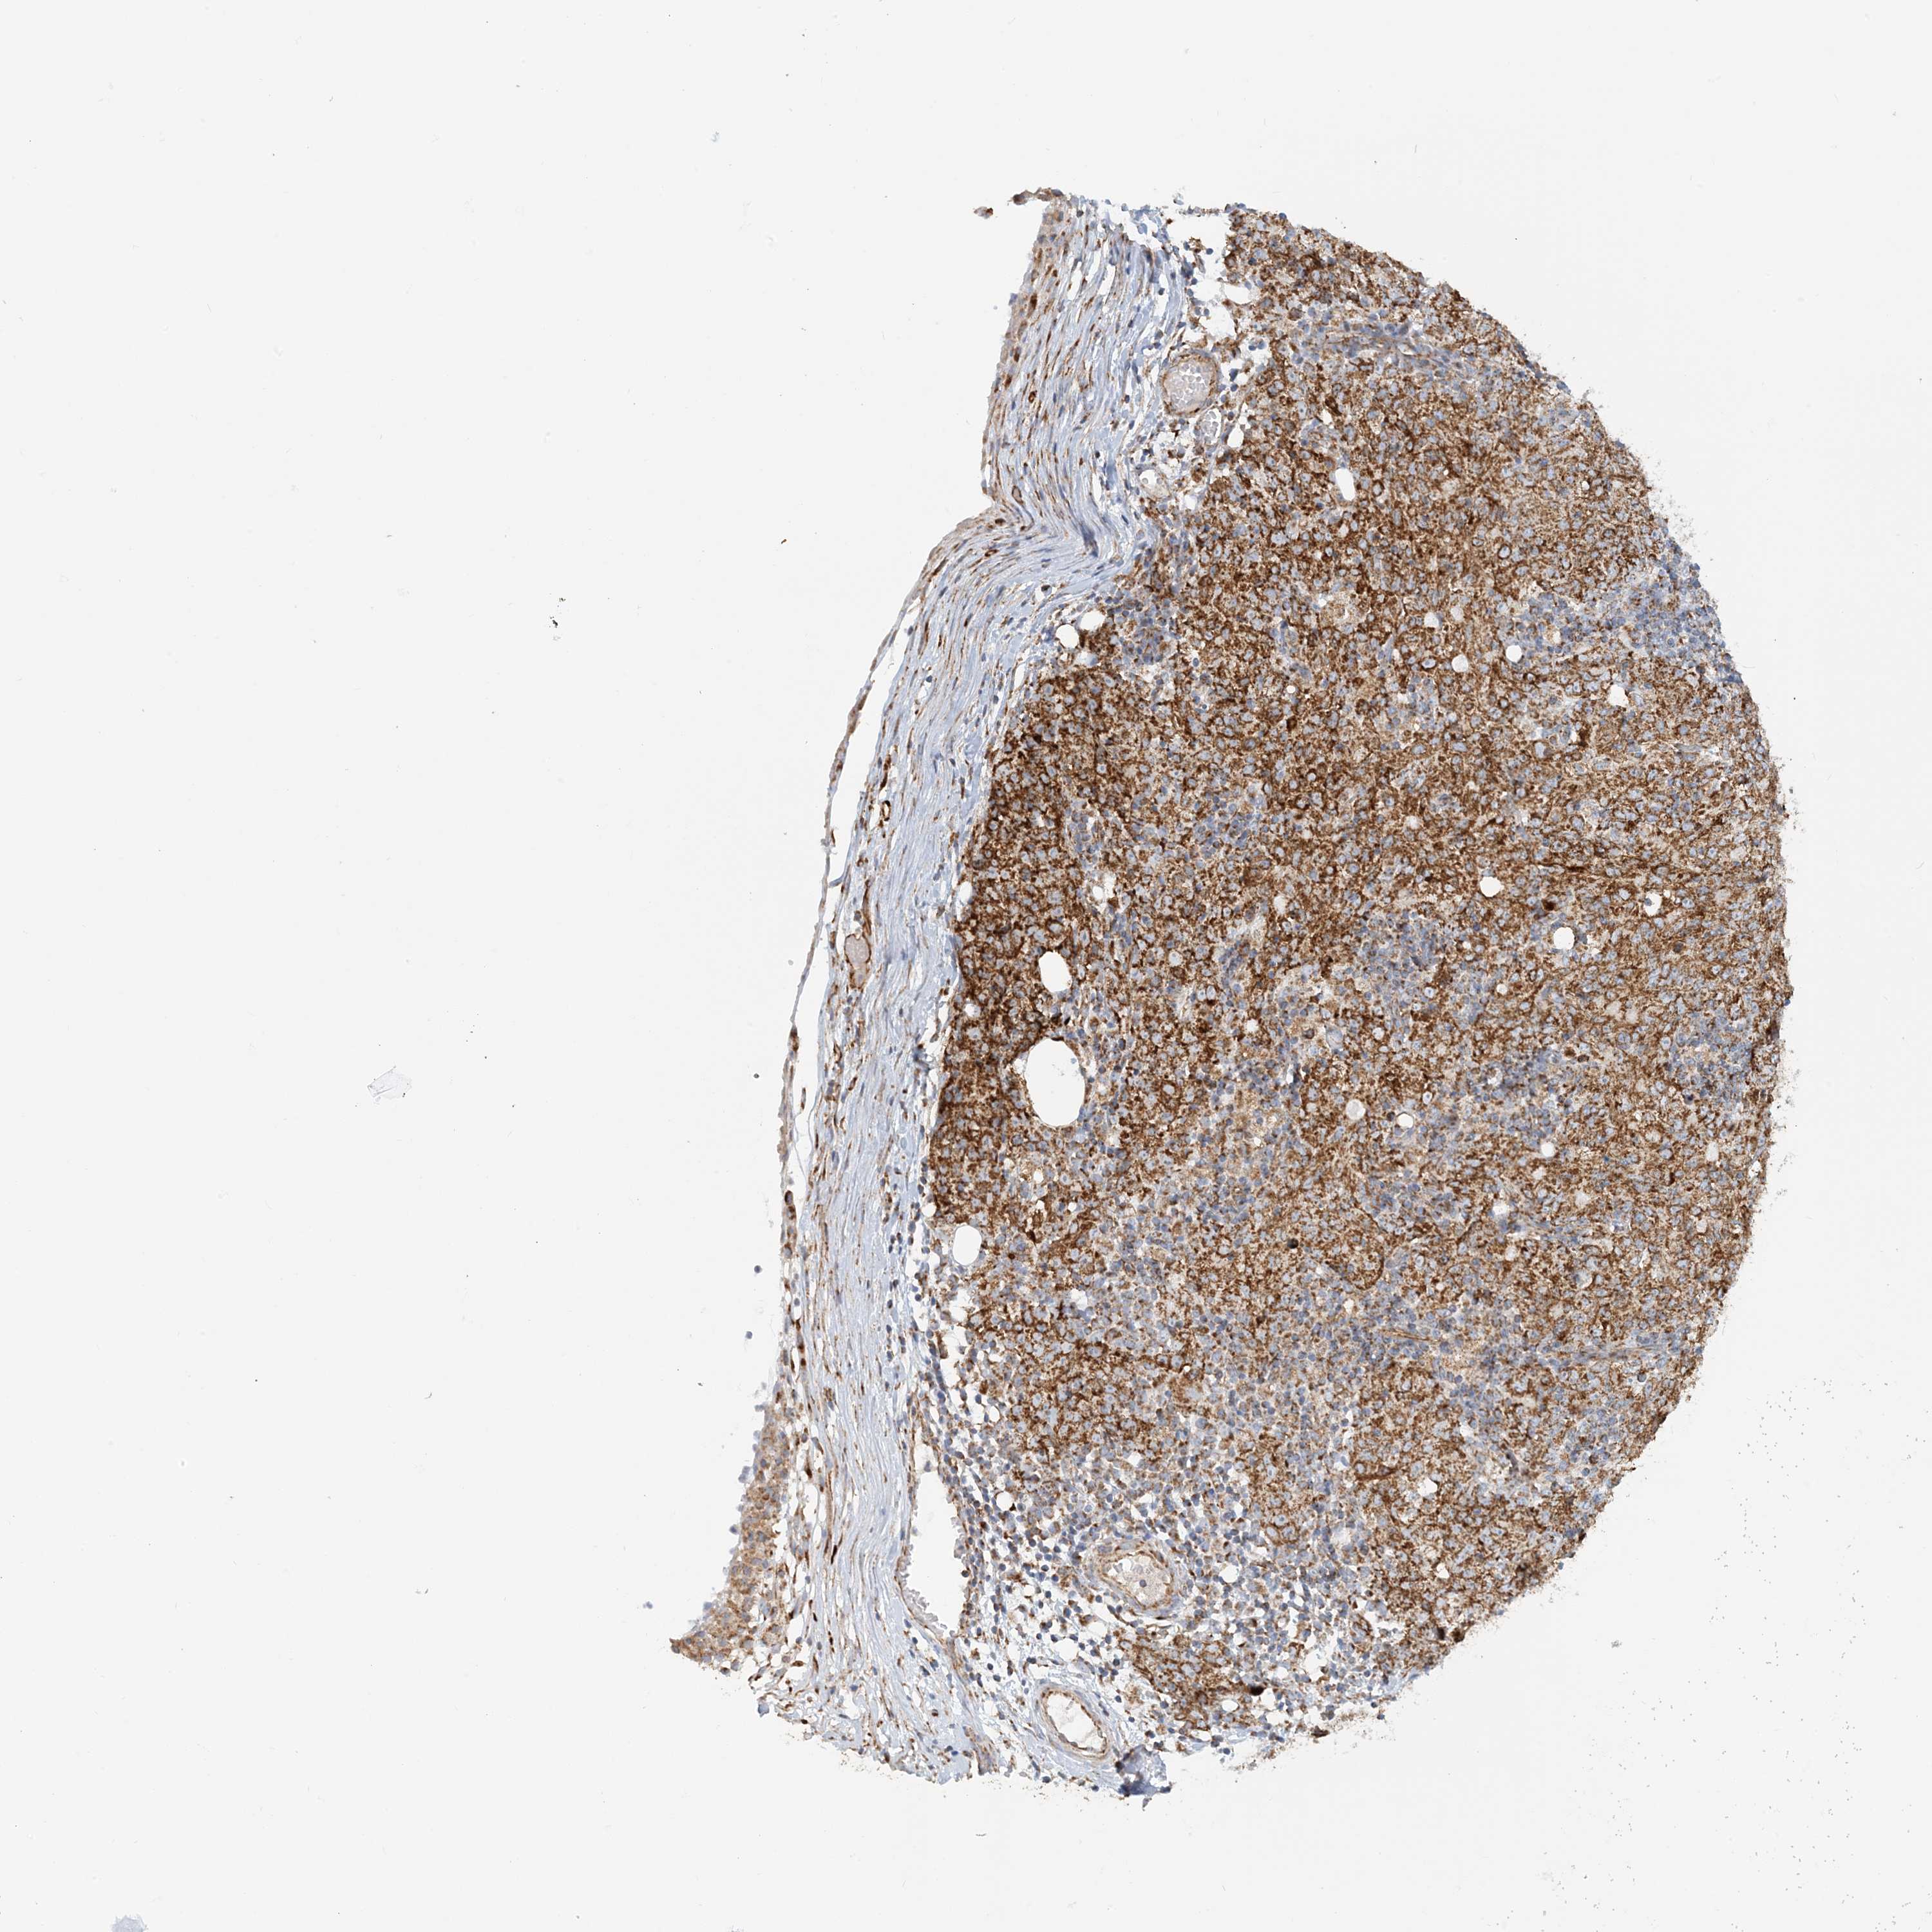

OVARIAN CANCER - Protein expressioni

A mouse-over function shows sample information and annotation data. Click on an image to view it in a full screen mode. Samples can be filtered based on level of antibody staining by selecting one or several of the following categories: high, medium, low and not detected. The assay and annotation is described here.

Note that samples used for immunohistochemistry by the Human Protein Atlas do not correspond to samples in the TCGA dataset.

Antibody stainingi

Antibody staining in the annotated cell types in the current human tissue is reported as not detected, low, medium, or high, based on conventional immunohistochemistry profiling in selected tissues. This score is based on the combination of the staining intensity and fraction of stained cells.

Each image is clickable and will lead to virtual microscopy that enables deeper exploration of all samples and also displays staining intensity scores, fraction scores and subcellular localization as well as patient and tissue information for each sample.

Antibody HPA031966

Staining

High

Medium

Low

Not detected

Intensity

Strong

Moderate

Weak

Negative

Quantity

>75%

75%-25%

<25%

None

Location

Nuclear

Cytoplasmic/membranous

Cytoplasmic/membranous,nuclear

Cystadenocarcinoma, serous, NOS

Carcinoma, endometroid

Cystadenocarcinoma, mucinous, NOS

Carcinoma, NOS